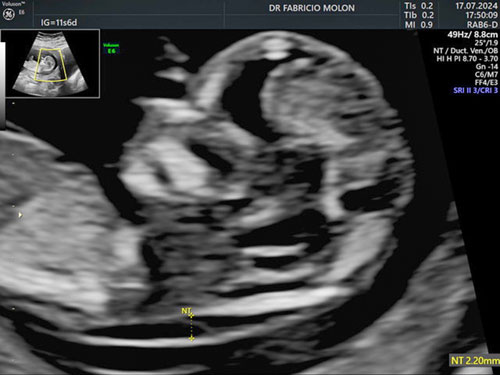

US Morfológica do 1º trimestre - Certificado pela Fetal Medicine Foundation

Avalia a morfologia do feto, faz o rastreamento cromossômico e o cálculo de risco para pré-eclâmpsia. É realizada entre 11 e 13 semanas e seis dias.

Algumas questões que vamos avaliar neste exame:

• A formação do bebê, com uma visão detalhada;

• A saúde da placenta e colo do útero;

• Cálculo de risco para parto prematuro, restrição do crescimento fetal e da pré-eclâmpsia.

• Cálculo de risco para doenças cromossômicas, uma delas sendo a Síndrome de Down.